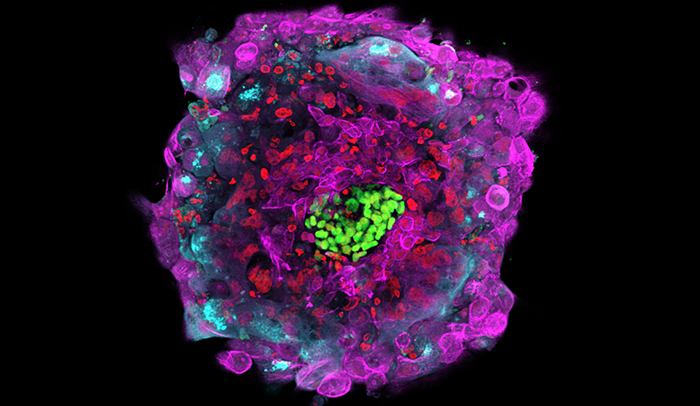

Early cellular distinction: Different cell types are shown above in an early human embryo, six days after fertilization. Cell boundaries are indicated in white, cells of the inner cell mass (which will give rise to the embryo proper) are in green, and trophoblast cells (which will give rise to extraembryonic tissues) are in purple and magenta.